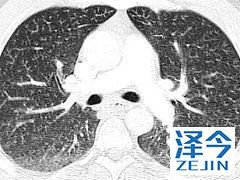

尼达尼布是一种小分子抗肿瘤多激酶抑制剂 尼达尼布已经被授予治疗特发性肺纤维化的孤儿药物,能够通过降低用力肺活量,减少疾病对患者的影响。不过不建议中重度的肝病患者使用,如果患者不确定自己是否能够使用,请在医生的指导下进行使用,并且在使用药物之前应做好避孕措施。

在3项随机,双盲,安慰剂对照临床试验(n = 1,231)中,使用尼达尼布治疗的特发性肺纤维化(IPF)患者的FVC年降低率(-60至-115 mL)显着降低。在调整性别,身高和年龄后,安慰剂(-191至-240 mL)。在3项临床试验中的2项中,尼达尼布也改善了52周内从基线开始的用力肺活量(FVC)变化百分比。II期和III期临床试验表明,与安慰剂相比,使用尼达尼布(HR 0.16; 95%CI,0.04至0.71)的患者首次急性IPF恶化的风险显着降低; 第三次临床试验(第三阶段)发现治疗组之间没有差异。尼达尼布不会影响全因死亡率。【乐伐替尼(E7080,Lenvima,仑伐替尼)适应症】(1)分化型甲状腺癌:单药用于局部复发/转移、进展的放射性碘难治性分化型甲状腺癌患者。(2)肾细胞癌:与依维莫司联合用于治疗后进展的肾细胞癌。(3)肝细胞癌。【乐伐替尼(E7080)治疗效果】国内不少患者对E7080的评价不错,尤其是肝癌和胆管癌的患者。大家对这个药物的总体印象是:有效率很高,不少患者的AFP会下降;起效快,大约10-15天可能就会看到效果;剂量和疗效正相关,大部分患者从13mg开始使用,如果无效可以加量到15、17或者20mg ,最高24mg;可以联合用药,比如联合雷利度胺或者184,可以提高有效率;副作用小,大部分患者可以耐受。